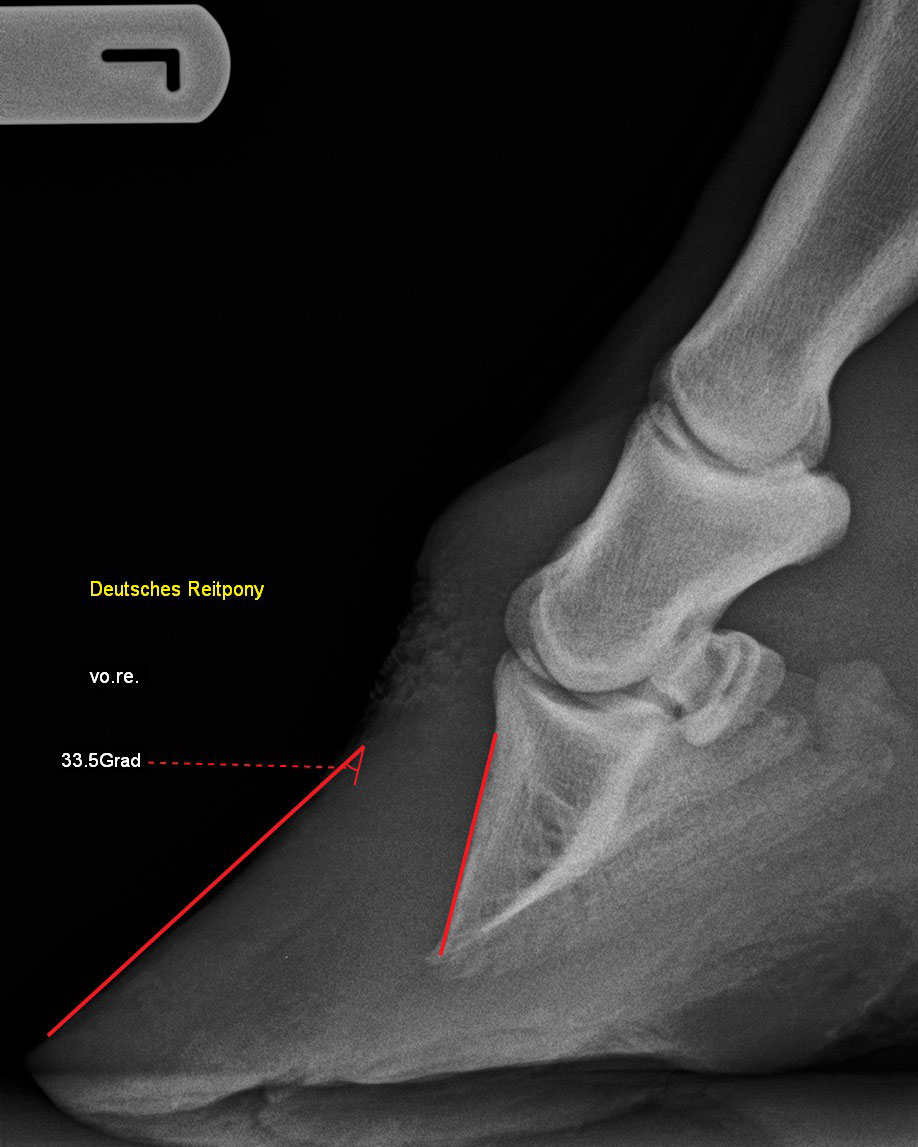

Zehe - 90°-Aufnahme

Hufrehe mit einer höchstgradigen Hufbeinrotation von 33,5 Grad